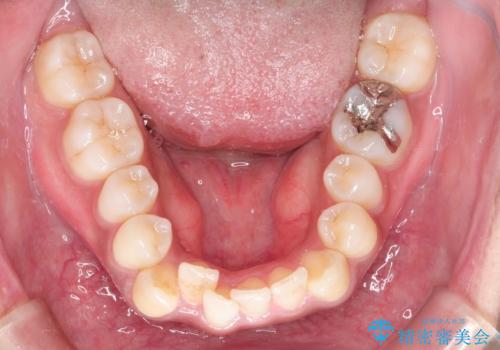

重なりが強い右側の上下の歯を1本ずつ抜歯する計画としました。

下顎はインビザラインのみで治療を行いました。